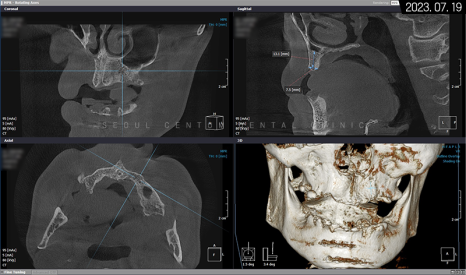

작년에 저작 기능과 치아 형태를 복구하고 싶은 마음에 저희 서울센텀치과를 찾아주셨던 50대 남성분이 계셨습니다. 시진(視診)을 통해 확인해도 전치부, 구치부 통틀어 많은 영구치가 소실되어서 간단히 식사하기조차 어려우셨으리라 봅니다.

앞니를 포함해 하악에 남아있는 영구치도 잇몸, 치조골 소실로 동요가 심하고 치주 질환을 동반하고 있어 뿌리만 고정된 상황이었습니다.

파노라마 엑스레이 사진을 보면 뿌리 주변이 골 소실로 인해 까맣다는 것을 확인할 수 있습니다.

그래서 아래턱을 보존할 수 없는 영구치를 먼저 발치하고 임시 틀니를 사용하면서 저작 기능을 갖기로 했죠. 상악은 픽스처를 고정했고 위턱뼈 어금니 위의 상악동막이 내려왔기 때문에 측방 상악동 거상술도 시행해야 했습니다. 나머지 치조체는 픽스처 고정 위치에 따라 치조정 술식으로 뼈이식재를 넣기로 했습니다.